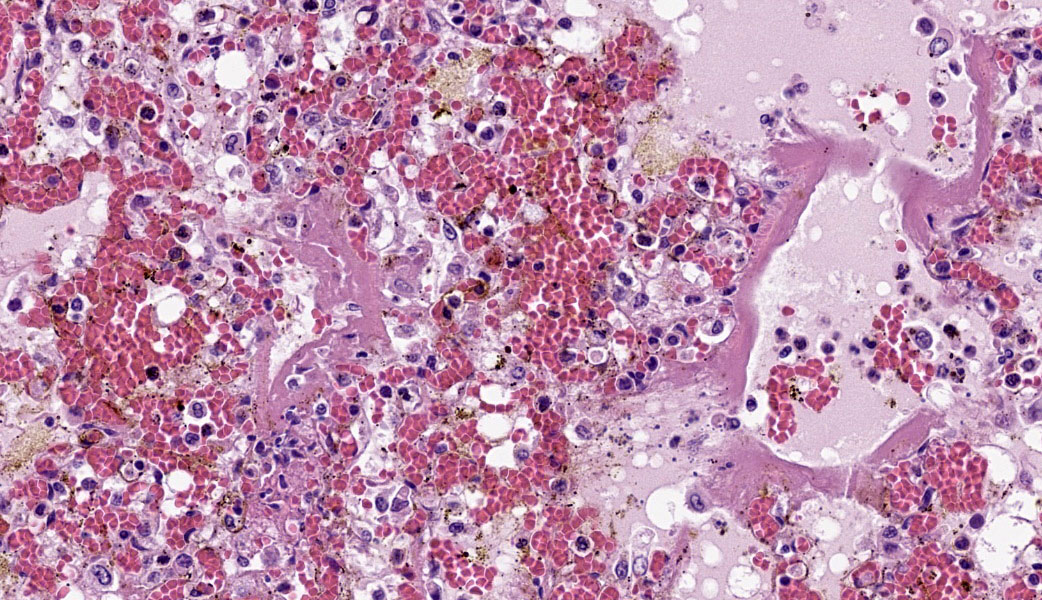

Typical pathological changes in equids with viral pneumonia include pulmonary consolidation in a lobular pattern separated by unaffected or overinflated lung lobules, or less commonly, a diffuse pattern of pneumonia.1 EIV infections complicated by secondary bacterial infections are characterized by fibrinosuppurative exudate and pulmonary consolidation, mostly restricted to the cranioventral pulmonary lobes (bronchopneumonia).1,12,13 Histopathologically, acute stages typically reveal rhinitis and tracheitis with epithelial necrosis and infiltrates of lymphocytes in the lamina propria. Subacute to chronic lesions consist of epithelial hyperplasia and squamous metaplasia.6,11 Affected lungs exhibit bronchointerstitial pneumonia with hyaline membranes in the alveoli, type II pneumocyte hyperplasia, and necrotizing bronchitis/bronchiolitis. Secondary bacterial bronchopneumonia may also develop.4,6,12

Lung: Pneumonia, bronchointerstitial, necrotizing and fibrinosuppurative, acute, multifocal to coalescing, marked, with thrombosis, edema, and hyaline membranes.

Determining differentials in a case of viral pneumonia in any species requires a working knowledge of viral pathogenesis and target cells to refine the list of potential offenders. In this case, the most striking hallmarks for influenza virus include the end-airway epithelial necrosis and patchy areas of hemorrhage. Influenza is both endotheliotropic and epitheliotropic and, while it affects epithelial cells in the upper airways, it has unique tropism for the type I and type II pneumocytes of the alveoli as well. It causes significant destruction to end-airways as a result. This key difference can help separate an influenza infection from other pneumotropic viruses, such as calicivirus in cats. (Feline calicivirus infection of the lung can look nearly identical to an H5N1 influenza virus infection in a cat, but the state of the end airways can help clue in the pathologist to which virus is most likely and can assist in decision-making for next testing steps. The more virulent strains of feline calicivirus can cause severe interstitial pneumonia, but they do not cause necrosis of end airways the way that influenza does.)